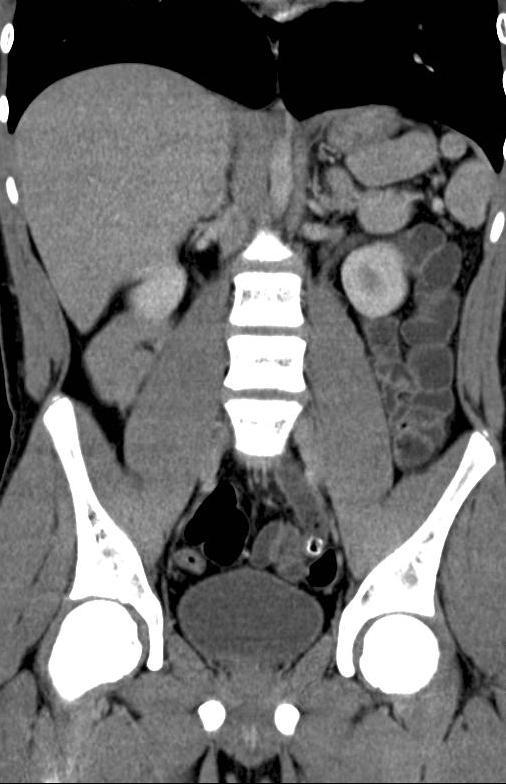

Pijn links onder in de buik NTVG Pijn Links Onder In Buik En Koorts 15 oorzaken & oplossingen bij lage buikpijn. U kunt ook problemen hebben met plassen, poepen en vrijen. Bij vrouwen kunnen de eileiders of eierstokken ook betrokken zijn. Deze pijn hangt vaak samen met de dikke darm of het colon. Dan kunt u bijvoorbeeld een blindedarmontsteking, een bloeding of. Lage buikpijn ofwel pijn in je onderbuik betreft meestal pijn vanuit. Als. Pijn Links Onder In Buik En Koorts.